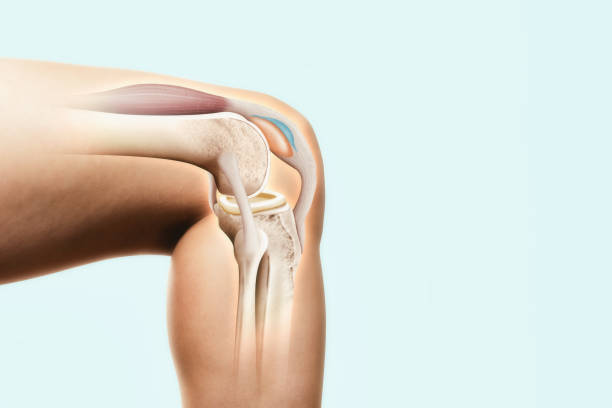

무릎연골은 무릎뼈에 가해지는 충격을 흡수하는 완충장치로 쓰면 쓸수록 닳을 수밖에 없습니다. 이러한 연골은 뼈와 유사한 성분이지만 뼈와 달리 칼슘을 함유하지 않아 뼈처럼 딱딱하지만은 않으며 탄력이 강하고 고무와 유사합니다. 이처럼 연골은 다쳐도 아프지 않기 때문에 치료를 늦추게 되고 병을 키우는 결과가 나올 수 있습니다. 하지만 연골 손상이 더 걱정되는 이유는 연골은 혈관이 없어 한번 손상되면 스스로 치유되거나 재생되지 않는다는 점입니다. 심한 경우에는 손상된 연골이 치유되지 않고 계속 퇴행하며 결국 퇴행성 관절염으로 진행됩니다.

무릎연골은 대퇴골과 경골을 각각 3~4mm 두께로 감싸 관절에 가해지는 충격을 흡수하여 관절이 원활하게 움직일 수 있도록 하기 때문에 심한 충격이나 잘못된 자세로 계속 자극하면 연골이 닳거나 부러질 수 있어 일상 생활에서 관리가 필요할 수 있지만 연골에는 신경이 없어 찢어지거나 닳아도 아프지 않아 연골이 마모되더라도 연골이 아픈 것이 아니라 아래의 뼈가 노출되어 통증을 유발하기 때문에 연골이 손상되었다면 스스로 치유되거나 재생되지 않는다는 점이기 때문에 미리미리 원인을 알고 대비해야합니다.